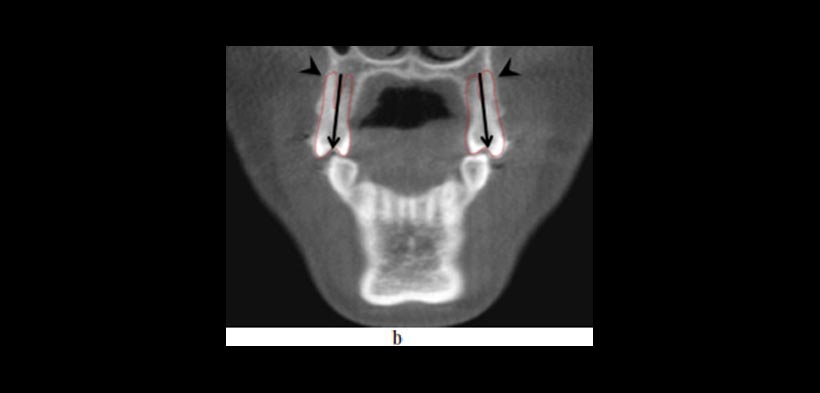

- EVALUACIÓN DE LA CALIDAD Y CANTIDAD ÓSEA: la determinación del volumen y la calidad del hueso, se han convertido en parámetros importantes en la prestación de tratamientos que usen dispositivos de anclaje (fig3).

Figura 3. La CBCT ofrece información sobre las condiciones de frontera que no son discernibles a partir de radiografías de rutina o durante el examen clínico, que pueden tener un impacto sobre las opciones de tratamiento. (a) Pre-tratamiento vista coronal que muestra la inclinación lingual (flechas) de los premolares maxilares y la proximidad de sus raíces bucales al margen de la cortical alveolar (puntas de flecha). (b) Post-tratamiento vista coronal que demuestra que las limitaciones ofrecidas por las condiciones de contorno relaciones hueso de la raíz se han abordado mediante torsión lingual de las raíces. (c) vista sagital y (d) vista transversal de la una CBCT de un individuo con limitaciones severas en las condiciones de contorno donde hay ausencia de corticales óseas. El tratamiento de ortodoncia estaría contraindicado en este caso.